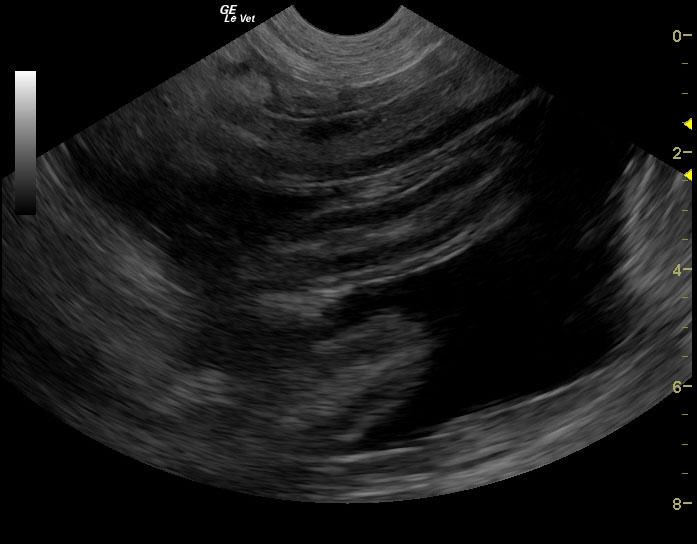

A 6-year-old female spayed Hound mix dog was presented for decreased appetite, increased drinking, and watery diarrhea for 4 days. Physical exam found soft, fluid filled bowels on abdominal palpation. An anti-diarrheal injection was administered, and the patient was discharged with oral anti-diarrheal medication, along with Tylan powder. Approximately 1 week later, the patient presented for persistent decreased appetite, lethargy, and watery stool. Physical exam found patient bright and alert, with pink mucous membranes, normal CRT, heart and lungs clear, a slightly distended abdomen, and no palpable masses found. Blood chemistry revealed hypoproteinemia, hypoalbuminemia, hypocalcemia, and hypocholesterolemia. CBC found high platelet count. Fecal was negative.